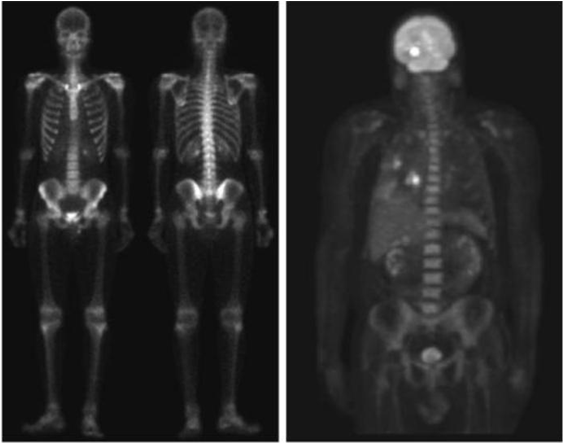

Gamma ray image

- 감마선의 투과성을 이용

- 주요 응용분야: 핵의학, 천문관측

a) 환자에게 감마선을 방사하는 방사선 동위원소를 주사, 감마 검출기로써 영상을 획득 - 병소의 위치 파악에 유용

b) PET(positron emission tomography) image

c) 백조자리 15,000년전의 가스성운의 감마선 영상

d) 핵반응 밸브로부터 나오는 감마선(밝은 부분)